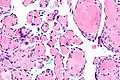

Intravascular papillary endothelial hyperplasia is a rare, benign tumor. It may mimic an angiosarcoma, with lesions that are red or purplish 5-mm to 5-cm papules and deep nodules on the head, neck, or upper extremities.[1][2]: 592

Histopathology Images